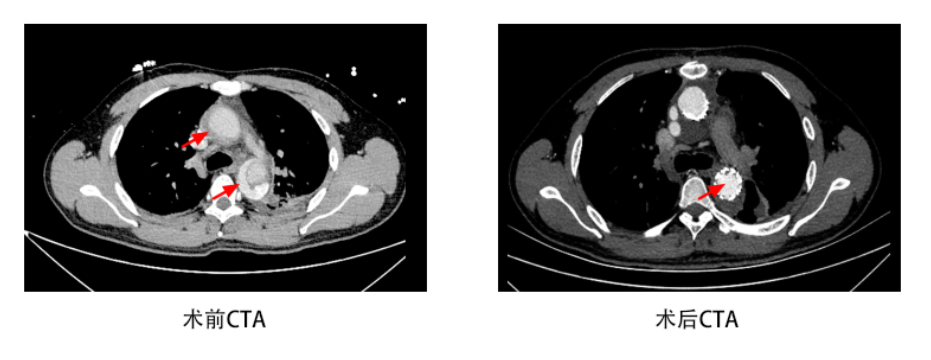

图中红色箭头所示术前夹层区域,术后完全恢复

经过充分的术前准备,我院血管外科团队,在麻醉科李健主任,手术室护理团队李毓敏护士长及体外循环团队的密切配合下,成功实施我院首例主动脉夹层A型复合手术。该手术采用在体外循环下,开放手术组和介入组密切配合,由孙元主任医师先进行心脏开口上方的病变升主动脉置换+全主动脉弓置换术。随后张喜成主任医师与黄献琛主任医师精准地用覆膜支架对远端的主动脉破口进行了封堵手术。在精细的手术操作、周密的麻醉和先进的体外循环设备保障下,整个团队密切配合,奋战5小时余,手术顺利完成。患者术后在重症监护室中在高建瓴主任团队的精心治疗下,恢复非常顺利,近日已康复出院,无任何并发症发生。